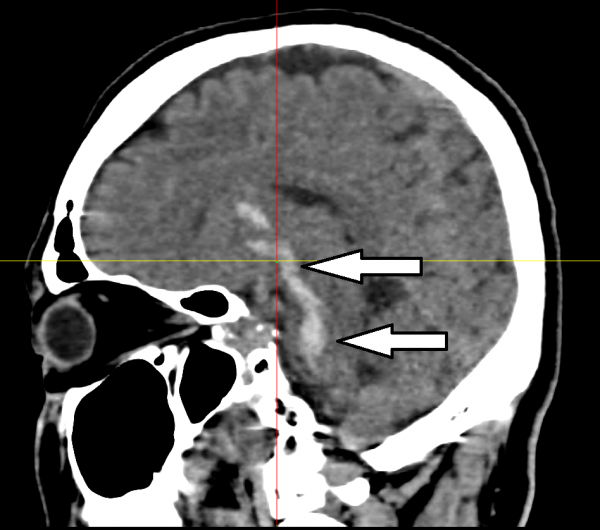

送到医院时,他已陷入重度,清醒指数只有3,无法自主呼吸,必须紧急插喉急救。血压则飙至220,电脑断层扫描时发现脑干中心的脑桥(pons)出血,证实是出血性中风,血块延伸至上端的基底神经节(basal brainstem),造成(Locked-in syndrome)。

脑桥出血,导致出血性中风,血块延伸至上端的基底神经节。